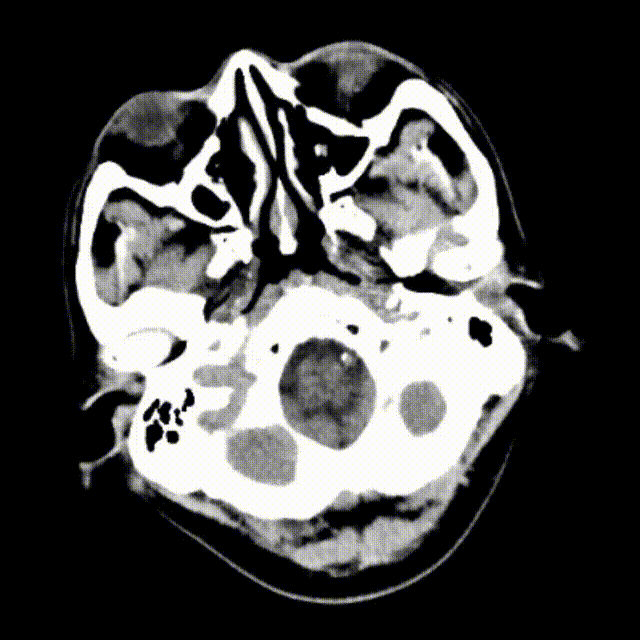

术前CT未见梗死灶。

头部MRI+DWI提示:左侧大脑半球多发脑梗死,DWI像与T2 FLAIR像不匹配。

头颈部CTA提示左侧颈内动脉闭塞。